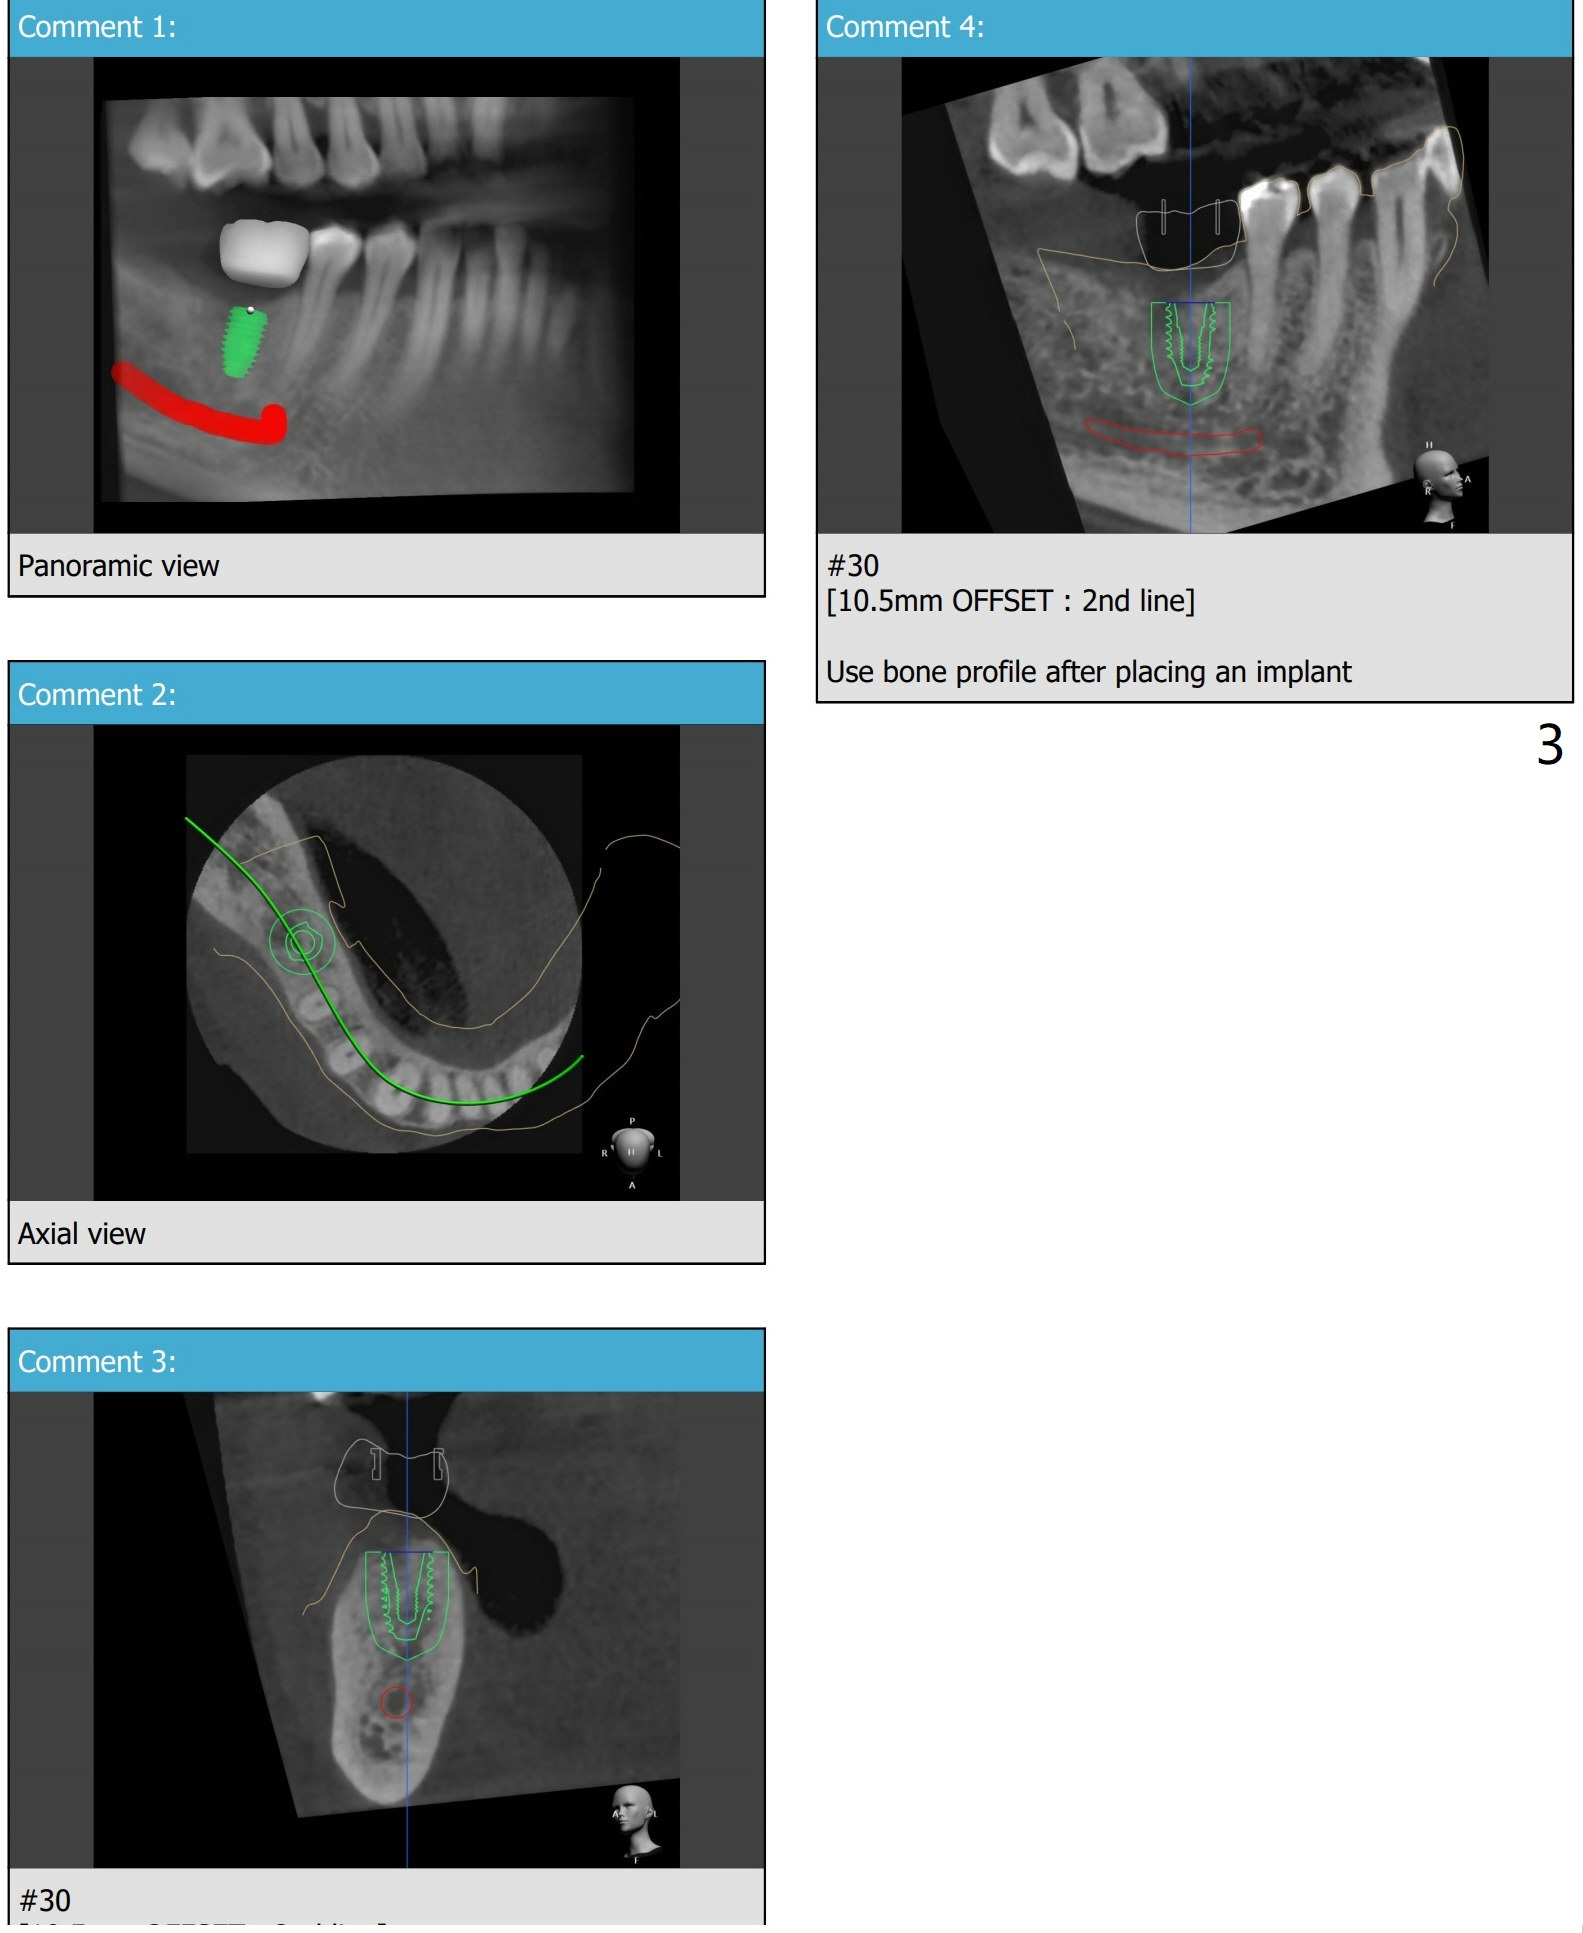

植体

近中牙槽嵴高,植牙后需要profile drill